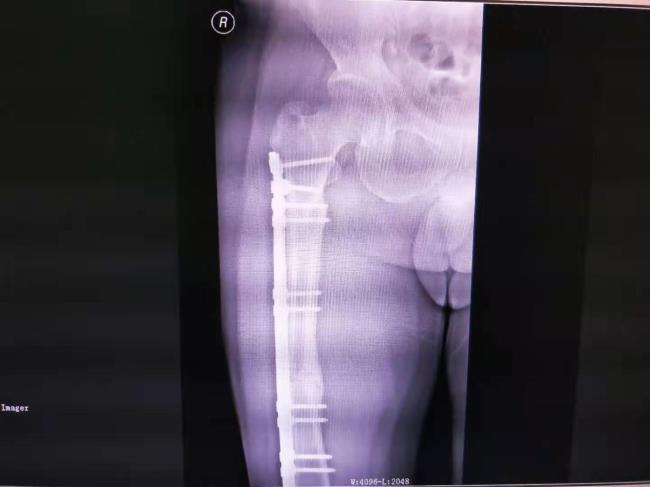

中医药结合桥接系统生物内固定技术治疗四肢骨折固定牢固,骨折愈合快,能早期康复,获广西医药卫生事宜技术推广奖三等奖。

病例2、左股骨骨不连治前及治疗后X线片